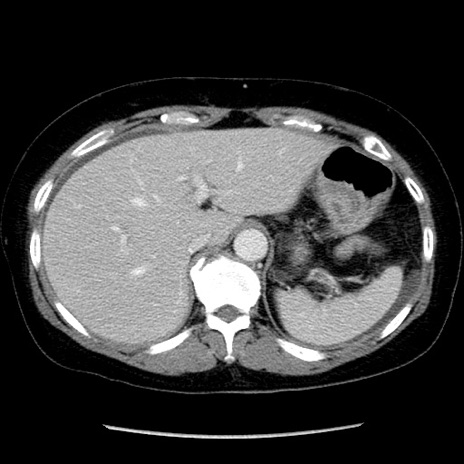

症例6(横断像)

【症例】50歳代女性

【主訴】下腹部痛

【現病歴】本日朝より下痢2回あり。 昼食を食べた後、嘔吐3回、下腹部痛認め、症状軽快せず、当院救急搬送。

最終食事:本日昼(生ものなし)。 昨日の夜、刺身を食ぺたとのこと。周囲に同様の症状の者なし。普段、排便は毎日あるとのこと。

【既往歴】卵巣癌術後(8年前に当院で卵巣摘出)

【身体所見】 意識清明、腹部:平坦、腸蠕動音→、やや硬、下腹部自発痛・圧痛あり、反跳痛あり、筋性防御なし。

【データ】WBC 16000、CRP 0.01